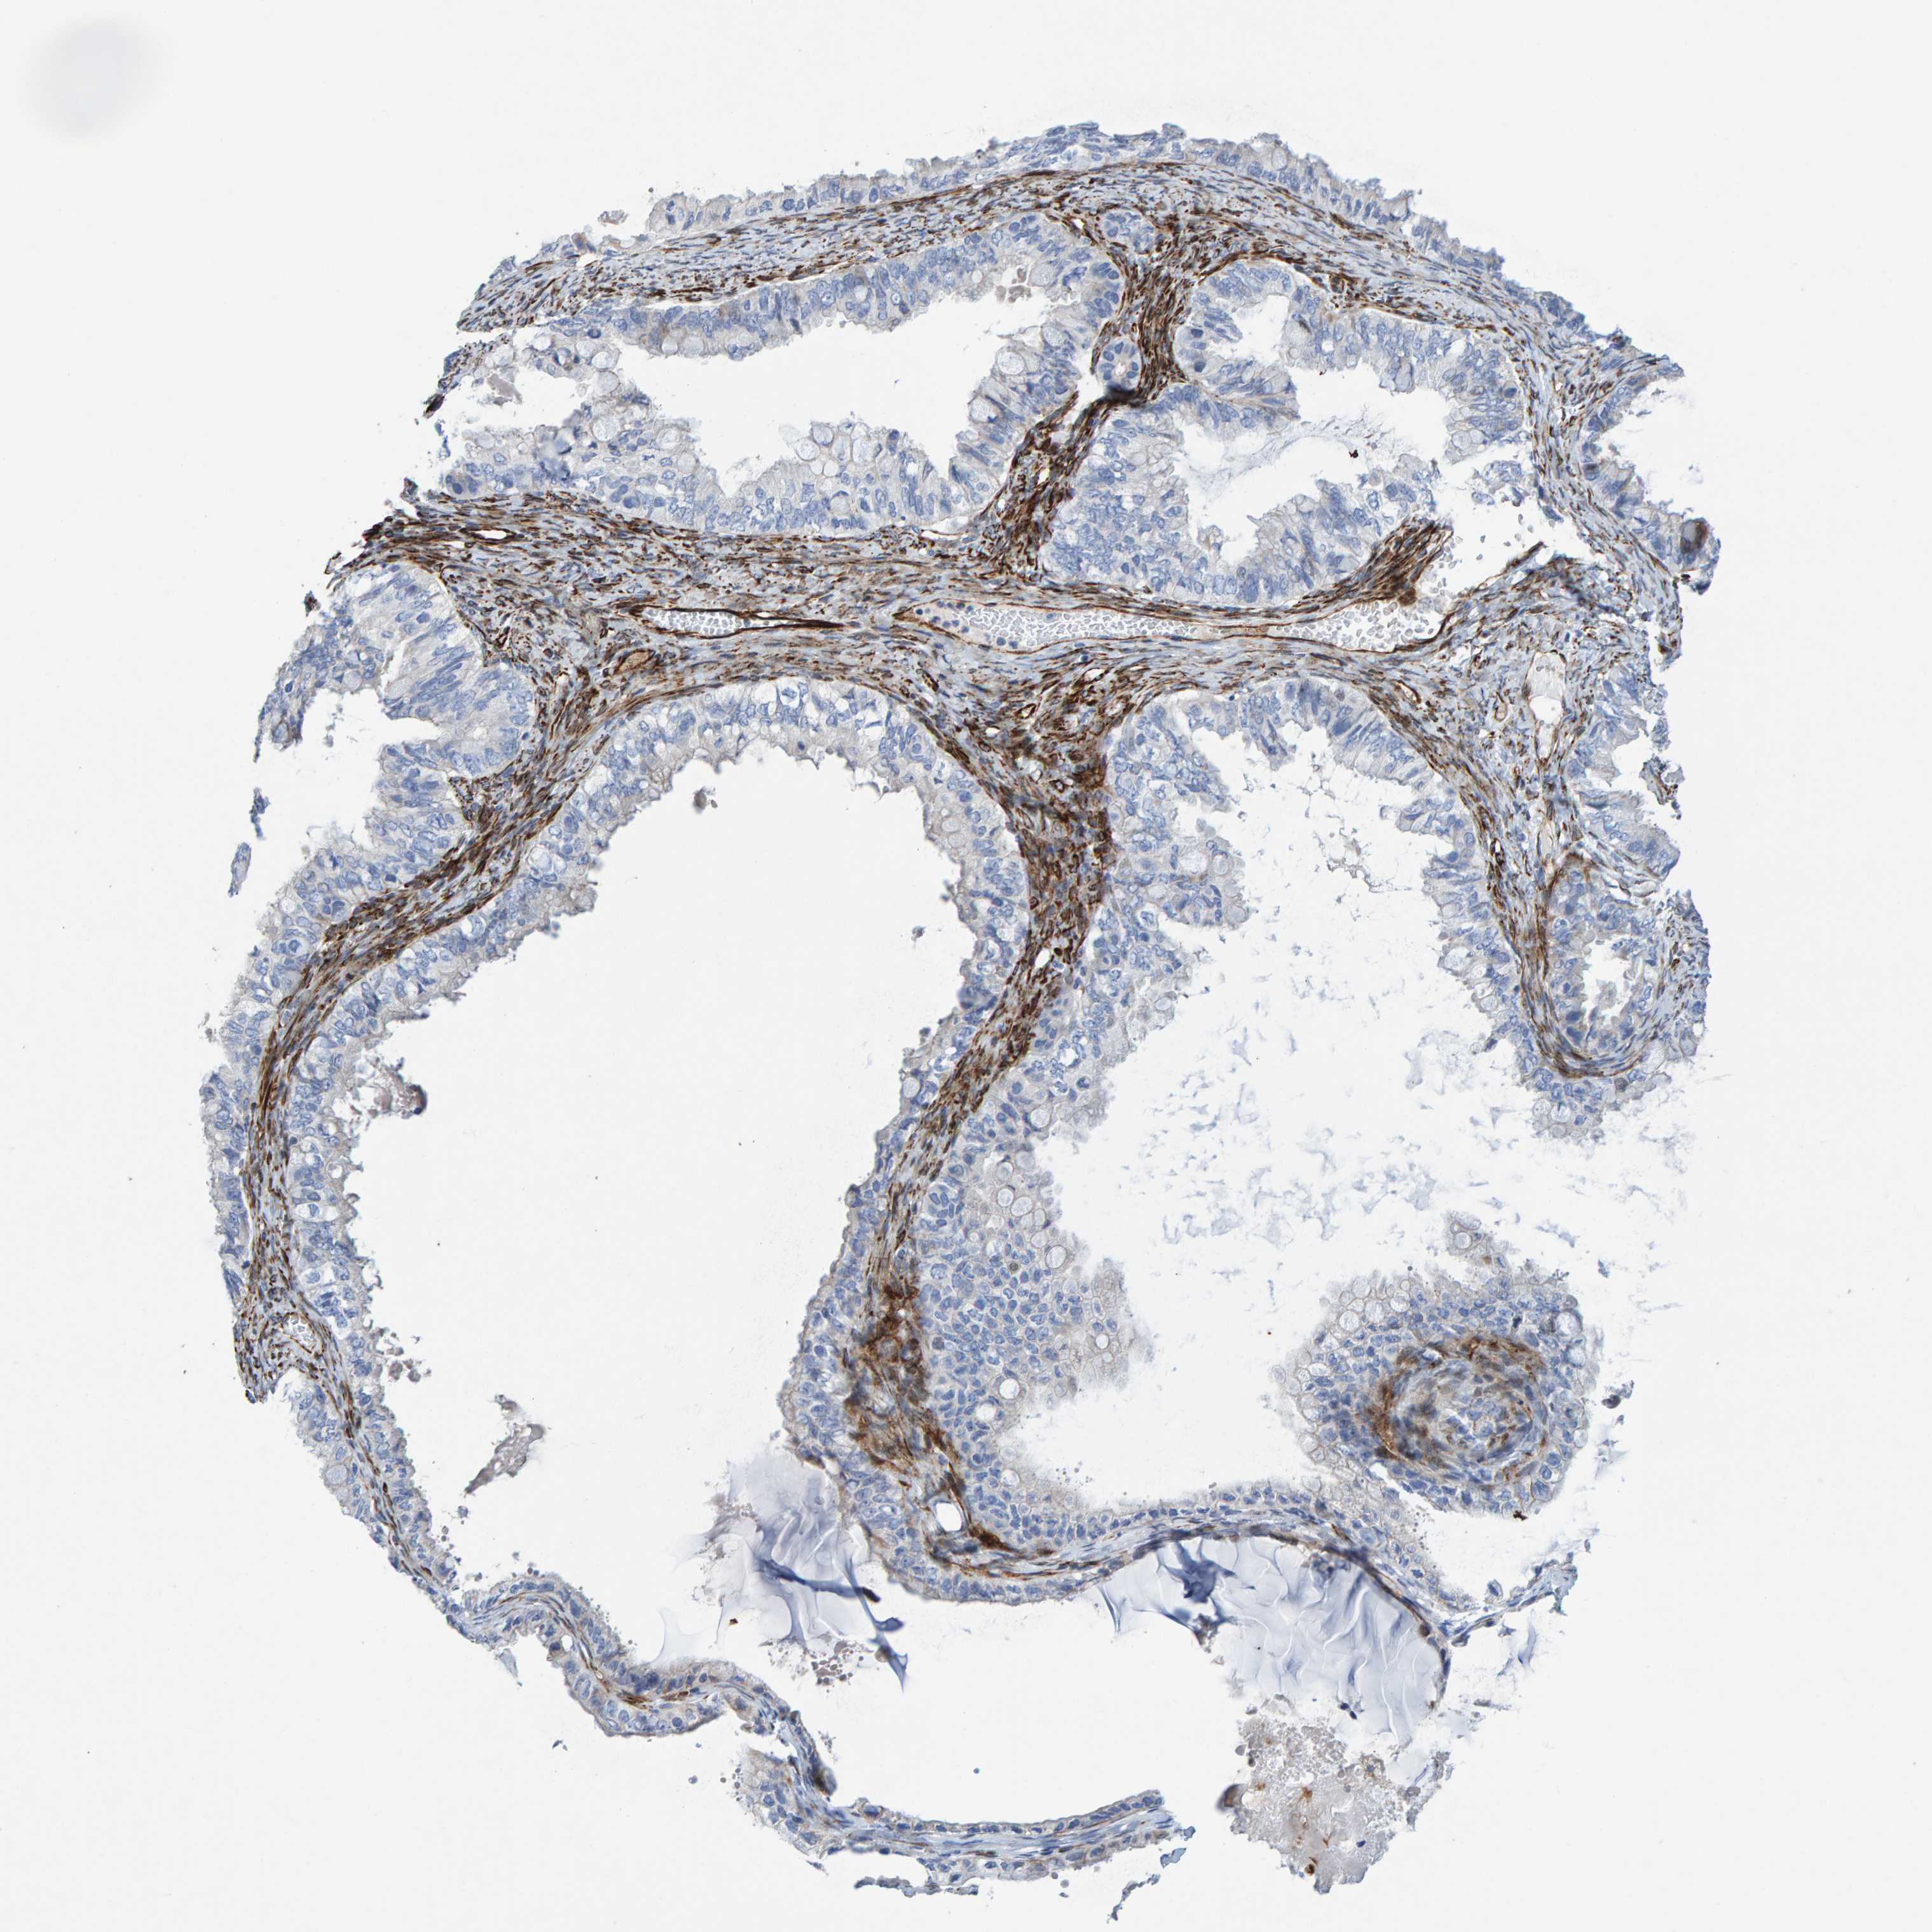

OVARIAN CANCER - Protein expressioni

A mouse-over function shows sample information and annotation data. Click on an image to view it in a full screen mode. Samples can be filtered based on level of antibody staining by selecting one or several of the following categories: high, medium, low and not detected. The assay and annotation is described here.

Note that samples used for immunohistochemistry by the Human Protein Atlas do not correspond to samples in the TCGA dataset.

Antibody stainingi

Antibody staining in the annotated cell types in the current human tissue is reported as not detected, low, medium, or high, based on conventional immunohistochemistry profiling in selected tissues. This score is based on the combination of the staining intensity and fraction of stained cells.

Each image is clickable and will lead to virtual microscopy that enables deeper exploration of all samples and also displays staining intensity scores, fraction scores and subcellular localization as well as patient and tissue information for each sample.

Antibody HPA023202

Antibody CAB017030

Cystadenocarcinoma, serous, NOS

Carcinoma, endometroid

Cystadenocarcinoma, mucinous, NOS

Carcinoma, NOS